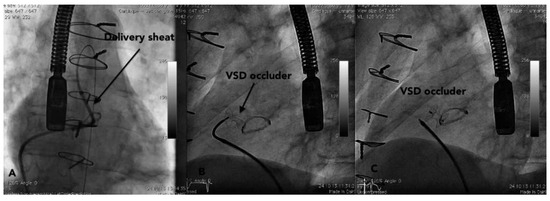

The fact that non-valvular (non-rheumatic) atrial fibrillation creates detectable thrombi in 17% of patients without oral anticoagulation and that 16% of the 17% (over 90% relatively) reside in the left atrial appendage (LAA), suggest that patients w...